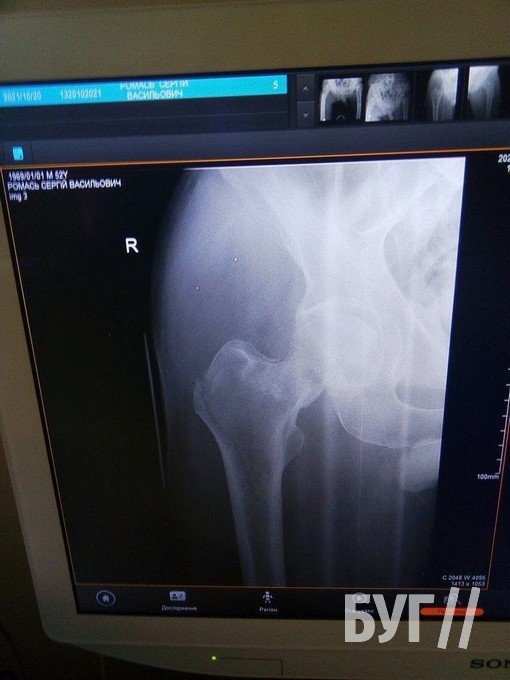

Колишній шахтар Сергій Ромась 20 жовтня отримав травму і потребує заміни суглоба і проведення операції.

У 52-річного чоловіка, який проживає у селі Суходоли, два переломи стегнових кісток і розтрощений кульшовий суглоб, пише БУГ.